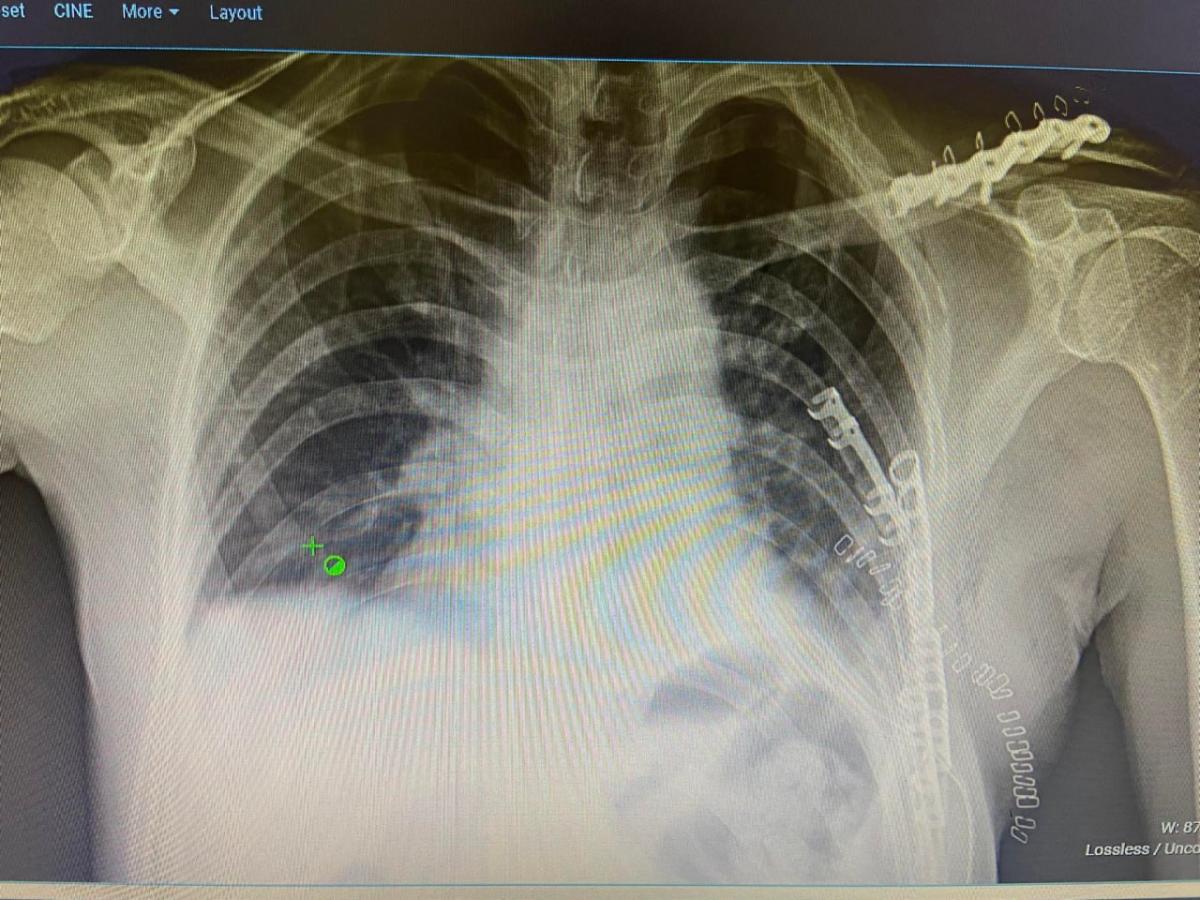

Мөн орон нутагт цээжний олон хавирганы зөрүүтэй хугарал, цээжний хөндийд шингэн хуралттай, цээжний хэнхэрцгийн хэлбэр алдалт оноштой үйлчлүүлэгчид хавирга хадах, эгэм хадах мэс заслыг орон нутагт анх удаа амжилттай хийлээ.